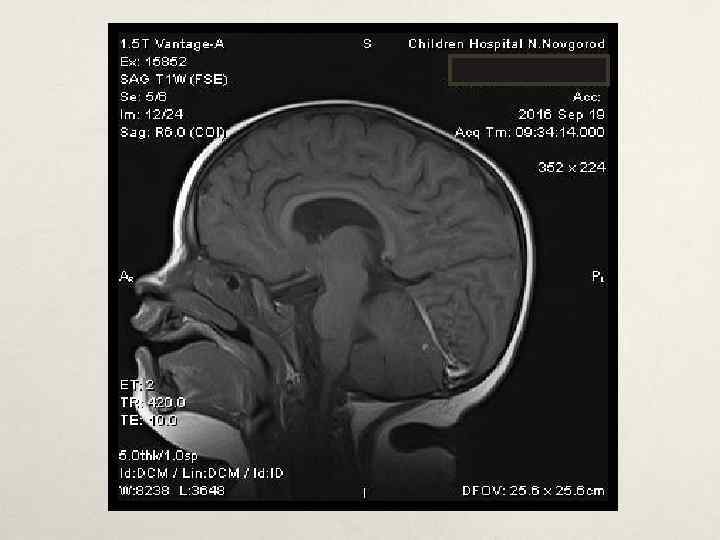

Клинический случай № 1 • В нейрохирургическом отделении: • МРТ головного мозга с КУ от 19. 05. 2016 – картина кистозно-солидного образования мозжечка, внутренняя окклюзионная гидроцефалия • Проведена операция – трепанация задней черепной ямки, удаление опухоли левой гемисферы мозжечка. Согласно гистологическому заключению и пересмотра препаратов в НИИ им. Бурденко – пилоидная астроцитома Grade I. МРТ головного мозга с КУ в динамике – остаточная опухоль 1. 7*1. 8*2. 3 см в левой гемисфере мозжечка. • • • В лечении: диакарб, аспаркам, дексазон, цефтриаксон, этамзилат, глюкозо-солевые растворы, СЗП, Er-масса, альбумин, симптоматическое. • В неврологическом статусе симптоматики, атаксии. регресс общемозговой